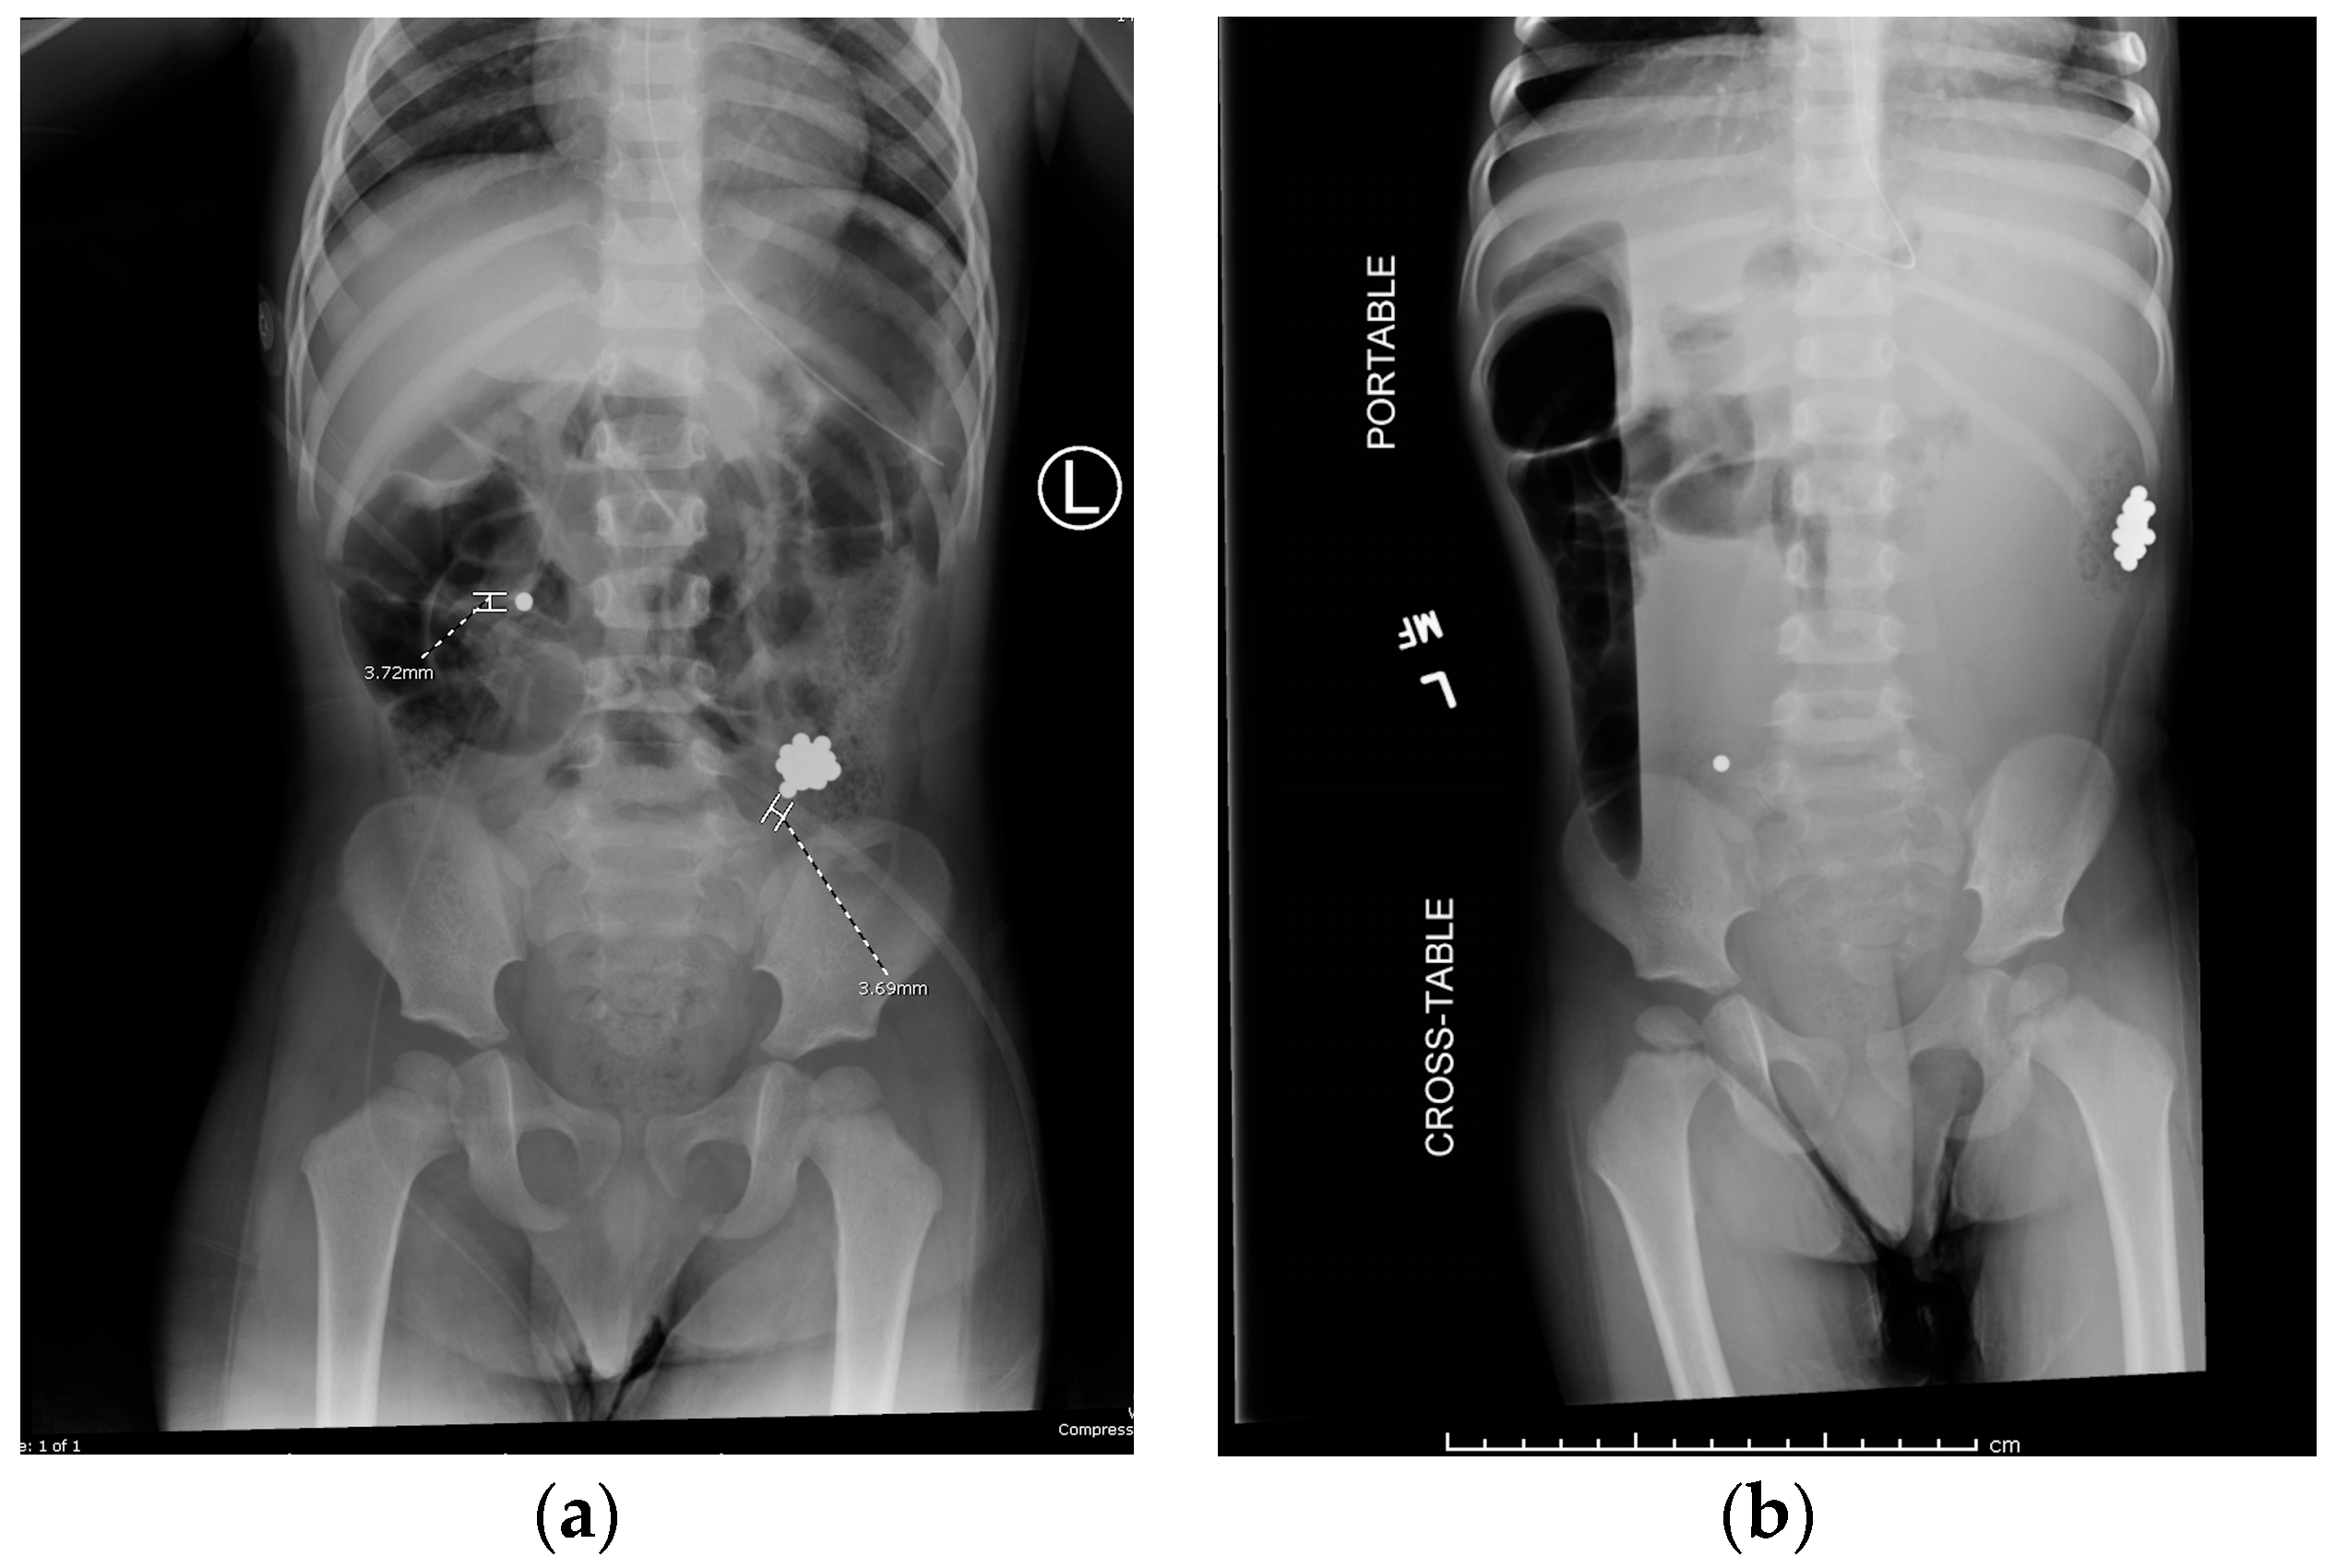

Colonoscopy was attempted by pediatric gastroenterology in an unprepped colon to avoid procedural delays. Due to formed stool, retrieval was unsuccessful. A nasogastric tube was placed for MiraLAX-based bowel prep, and serial abdominal x-rays were performed (Figure 4a,b). This approach aligns with conservative management strategies reported in the literature [3,11].

Figure 4. Abdominal radiographs before (a) and after (b) colonoscopy.